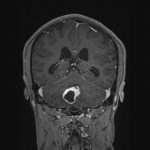

No.’25_82 手術前1

No.’25_82 手術前2